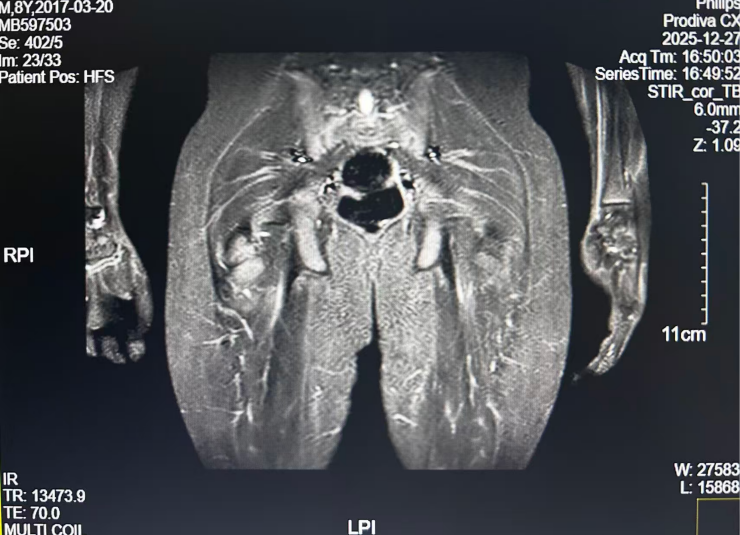

现病史与既往史:初诊1月余前游玩时自诉右下肢疼痛,呈持续性疼痛,性质不详,休息后无法缓解,无发热、腹痛等症状。双侧髋关节MR(2021.1.6)提示“双侧髂骨、坐耻骨、股骨及其骨骺、骶尾椎及所见腰椎广泛骨质破坏,伴周围软组织肿胀”。腹部B超(2021.1.8)提示“右侧后腹膜低回声包块”。既往史无殊。

PET/MR(2021.1.11)

腹膜后右侧肾上腺区不规则团块,FDG代谢增高,考虑恶性病变,神经母细胞瘤可能性大,建议结合病理;腹膜后腹主动脉右旁数枚肿大淋巴结,FDG代谢增高,考虑转移;全身骨骼FDG代谢弥漫性增高,考虑骨髓浸润。